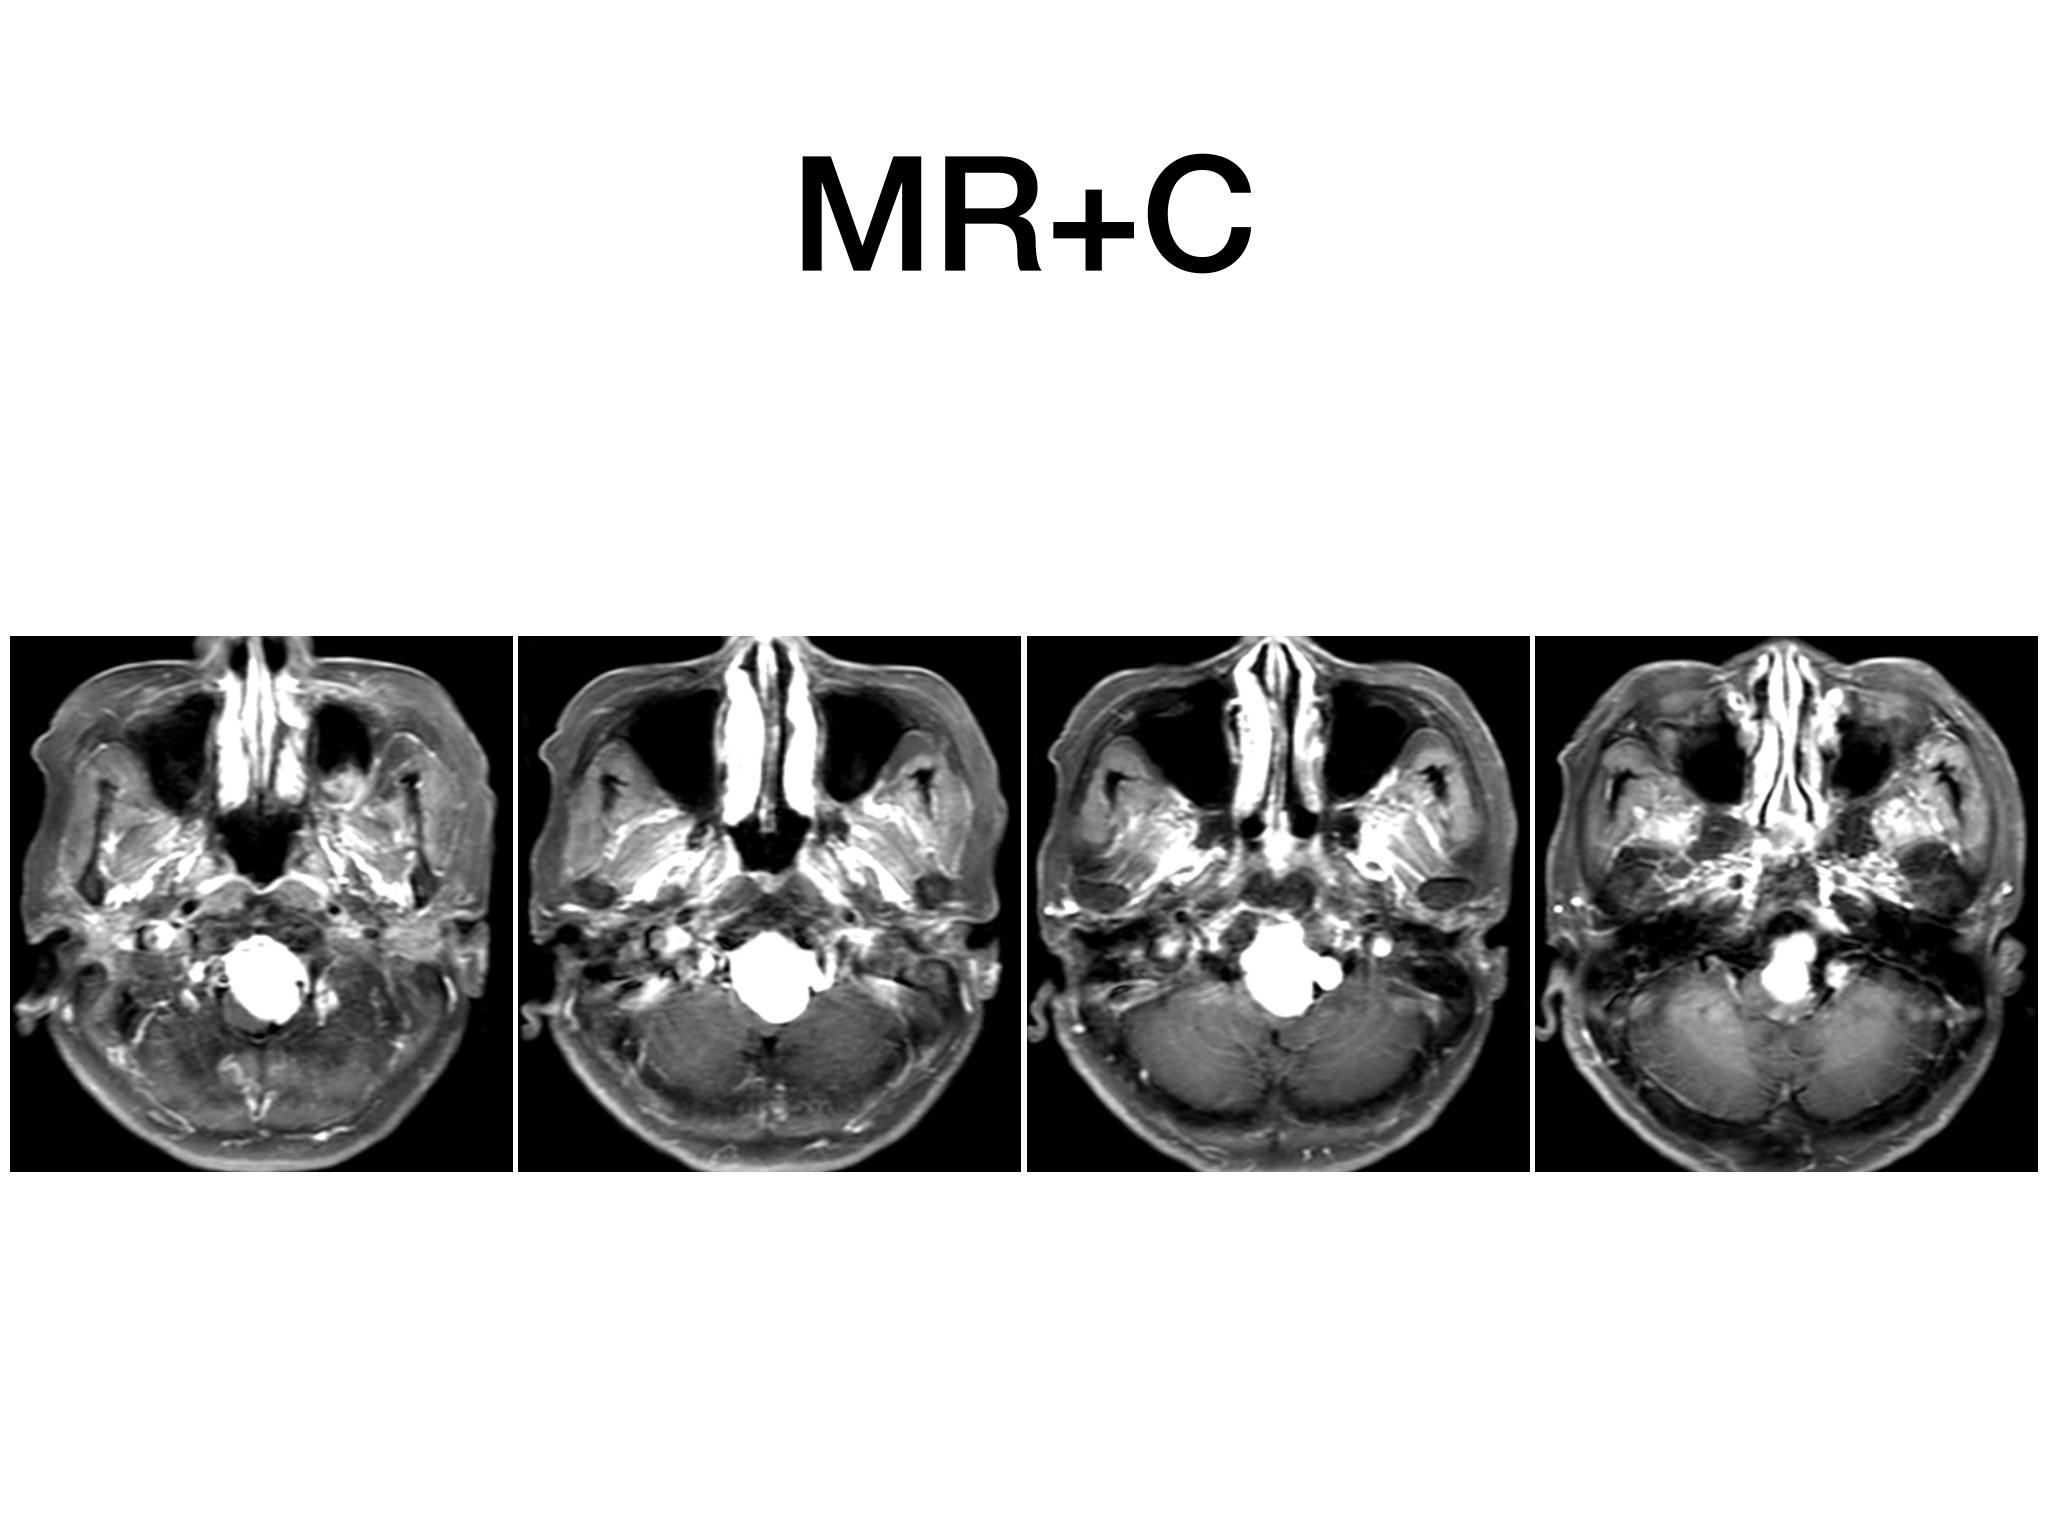

汇报一例后颅底肿瘤手术。为枕骨大孔巨大腹侧型脑膜瘤,该患者高龄,同时合并肺Ca,术前2周急性加重,枕骨大孔疝前期表现,术前已有延髓压迫及后组颅神经麻痹表现。经详细评估后采用远外侧经髁窝入路,最大化显露,重点保护延髓、后组颅神经,尽可能“零骚扰”。术中肿瘤质地韧,血供一般,与肿瘤上极与后组颅神经黏连紧密,最终99%切除,残留约1%,术后顺利康复出院,无新发症状,为后续进行肺部病变化疗创造有利条件。

远外侧经髁窝入路切除大型枕骨大孔腹侧脑膜瘤